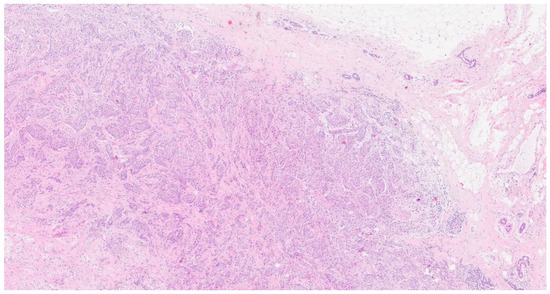

2. Case Presentation